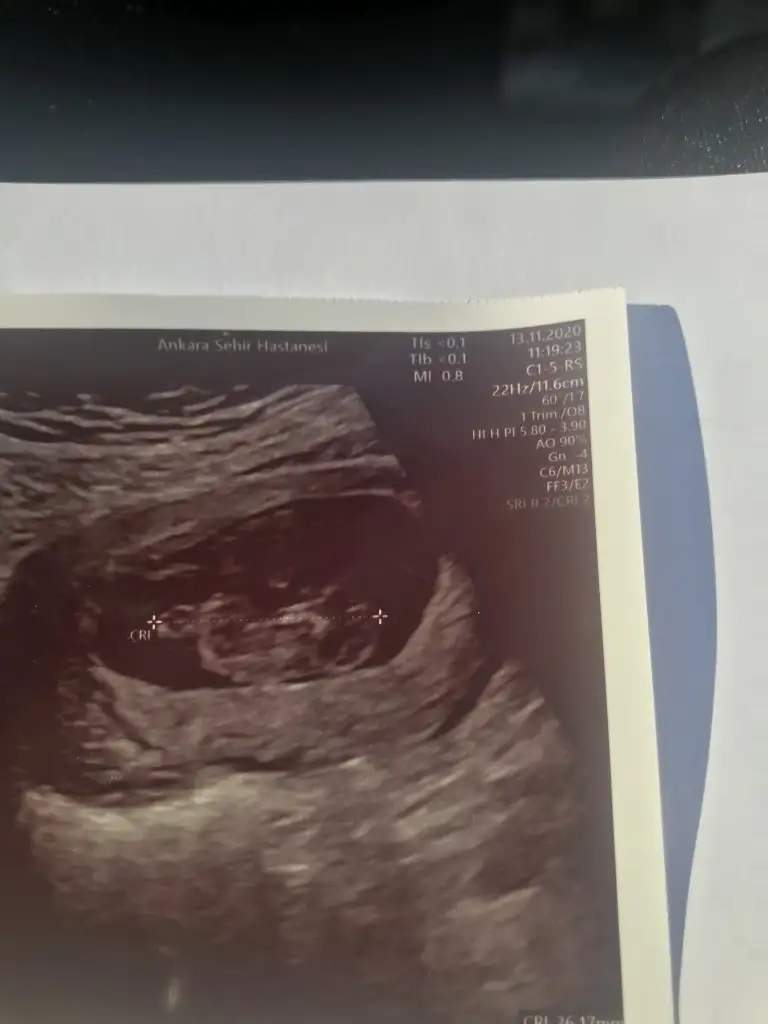

Teyzesi son postumdada yeni ultrason goruntuleri var :) Net birşey yok hala. Beklemedeyiz cinsiyet icin. Ona da bakarsan cook sevinirim...

Benim ultrason kağıtlarına da bakar mısınız?